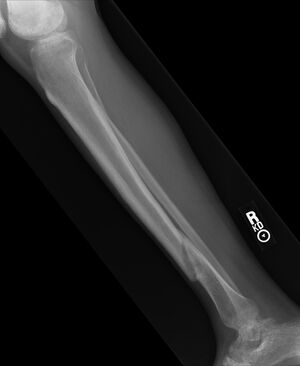

Gebrochenes Schienbein - rearl www.flickr.com, CC BY-SA 2.0

Ruhigstellung, Schienung, anschließend Transport ins Krankenhaus. Da die betroffene Stelle auf keinen Fall belastet werden sollte, empfiehlt sich der Abtransport der betroffenen Person mit einer Trage. Im Falle einer Ohnmacht oder einer möglichen Wirbelsäulenverletzung darf der Abtransport nur durch Fachleute (Sanitäter, Notärzte) vorgenommen werden.

Mit Hilfe einer Röntgenaufnahme wird der Schweregrad der Verletzung abgeklärt. Es erfolgt entweder eine Behandlung mit Gips oder eine operative Versorgung. In der Rehabilitation unterstützen Mobilisations-, Kräftigungs-, Koordinations- und Ausdauerübungen den Heilungsprozess wesentlich. Die volle sportliche Belastbarkeit ist, je nach Bruchart, erst nach vielen Wochen der völligen Bruchheilung gegeben.